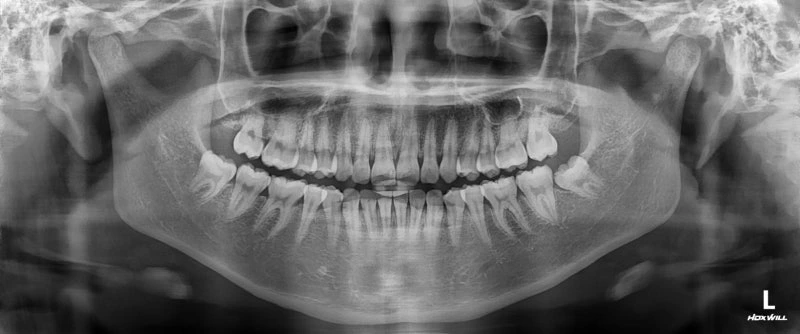

놀라운 사실은 치아를 잇몸과 턱뼈에 고정시키는 치주인대까지 이완시킨다는 것입니다. 실제로 임신 중 "치아가 흔들린다"고 호소하는 여성들이 있고, X-ray 검사로도 치아의 위치 변화가 확인된 사례들이 보고되고 있어요.